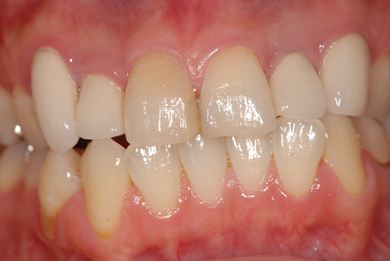

主訴 前歯2本の黄ばみが気になる。

治療前

• 治療前